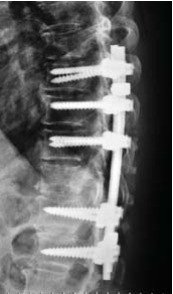

Madam B, a 72-year-old female, presented to my clinic recently with 3 months history of low back pain radiating to her left supra-iliac region. Her symptoms had worsened progressively. She had tenderness elicited by lumbar spine flexion. Neurological examination of her lower limbs was normal. X-ray and MRI of her spine revealed an extensive infiltrative lesion of T11 vertebral body, and its left pedicle. The posterior wall of the vertebra was eroded, and the lesion was encroaching onto the spinal cord and compressing it. The assessment was an extensive T11 spinal metastasis with cord compression and high risk of pathological fracture that could result in paralysis. Madam B underwent T11 decompression laminectomy with clearance of tumor tissue immediately surrounding the cord. The spine was instrumented from T8 to L1 segments to provide stability and to pre-empt pathological fracture. Frozen section of the specimen taken during surgery indicated the lesion to be lymphoma. This was later sub-typed as diffuse large B-cell lymphoma. Her back pain resolved completely following the surgery and she was ambulating well. She was referred to hematologist for outpatient chemotherapy treatment which started one week following the surgery.

Surgical approaches may be anterior or posterior. Sometimes a combination of both approaches is necessary. Surgery is needed if patient presents with deteriorating neurological deficit due to spinal cord compression, or when there is imminent risk of pathological vertebral fracture. Radiotherapy or chemotherapy may not be able to remove the tumour compressing the cord fast enough. They also can not address the pain arising from spinal instability due to pathological fracture. Speedy surgical decompression is needed in such circumstance to preserve the spinal cord function. Following surgery, patient will have good pain relief and can be treated with chemotherapy or radiotherapy without fear of losing the neurological function.